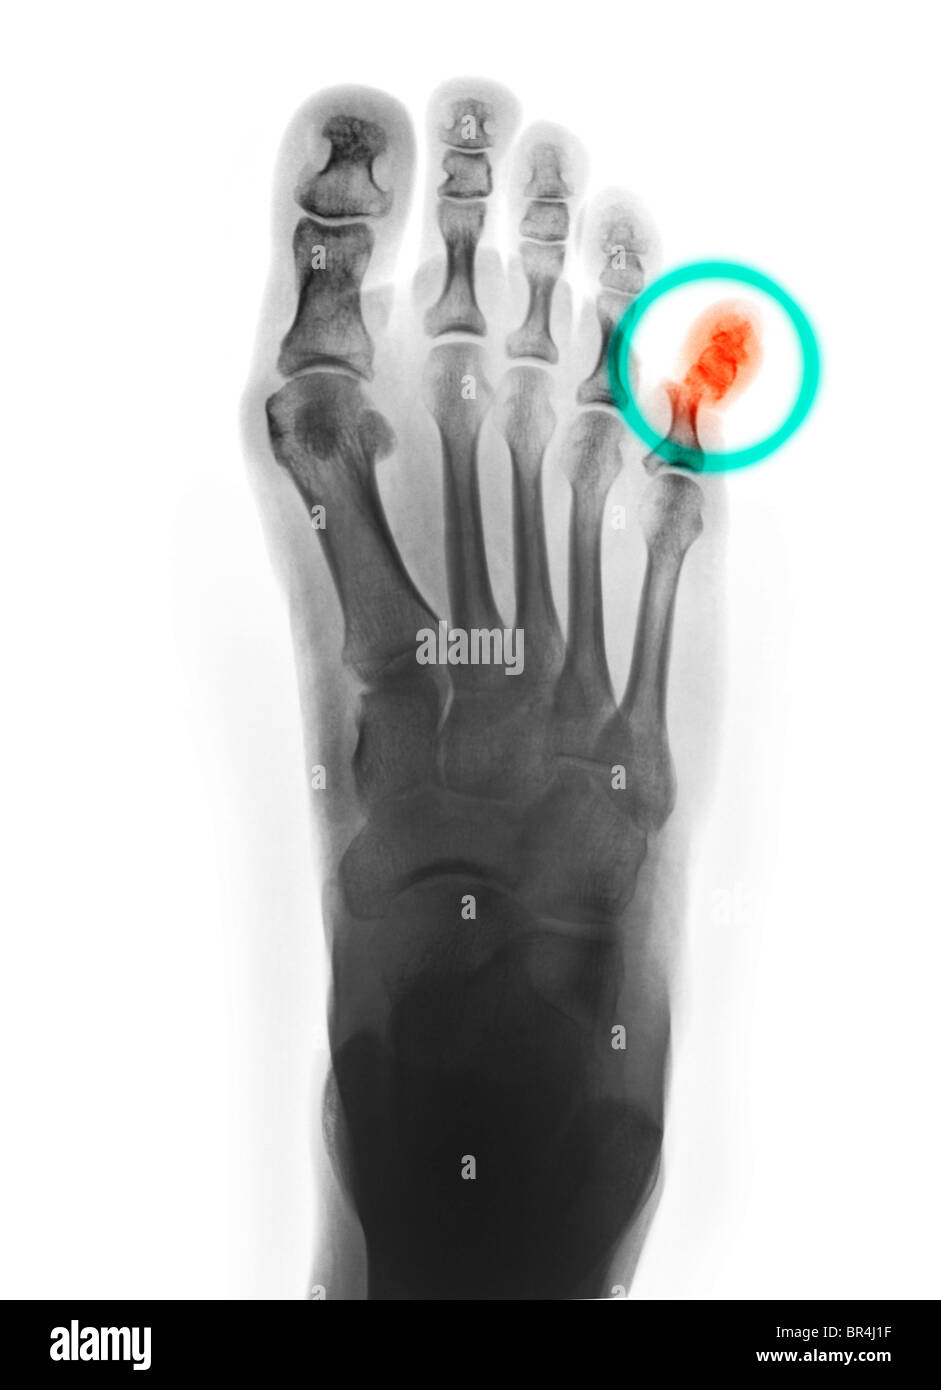

RMBR4J1F–Fuß Röntgen einer 53 Jahre alten Frau, die ihren Fuß schlug und der proximale Phalanx von ihrem kleinen Zeh gebrochen